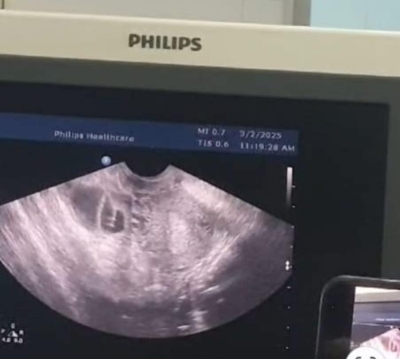

المرفأ …أجرى فريق طبي متخصص من وحدة أطفال الأنابيب بدائرة النسائية والتوليد ولأول مرة في الخدمات الطبية الملكية، عملية سحب بويضات لفتيات غير متزوجات عبر المستقيم

(Transrectal Oocyte Retrieval)، مهددات بفقدان القدرة الإنجانية مستقبلاً، أو يرغبن في تأجيل الإنجاب لظروفٍ خاصة، وذلك للحفاظ على بقاء فرصة الإنجاب قائمة.

وأكد رئيس اختصاص العقم أن العملية نُفذت بدقة عالية وتحت توجيه الموجات فوق الصوتية من قبل فريق طبي متعدد التخصصات من أطباء العقم، الأشعة، والجهاز الهضمي، وأن هذه الخطوة تمثل نقلة نوعية في طب الإخصاب والعقم، وتعزز من مكانة الخدمات الطبية الملكية كمركز رائد في تقديم الرعاية الصحية التخصصية بأعلى المعايير الأخلاقية والطبية على مستوى الأردن والمنطقة.